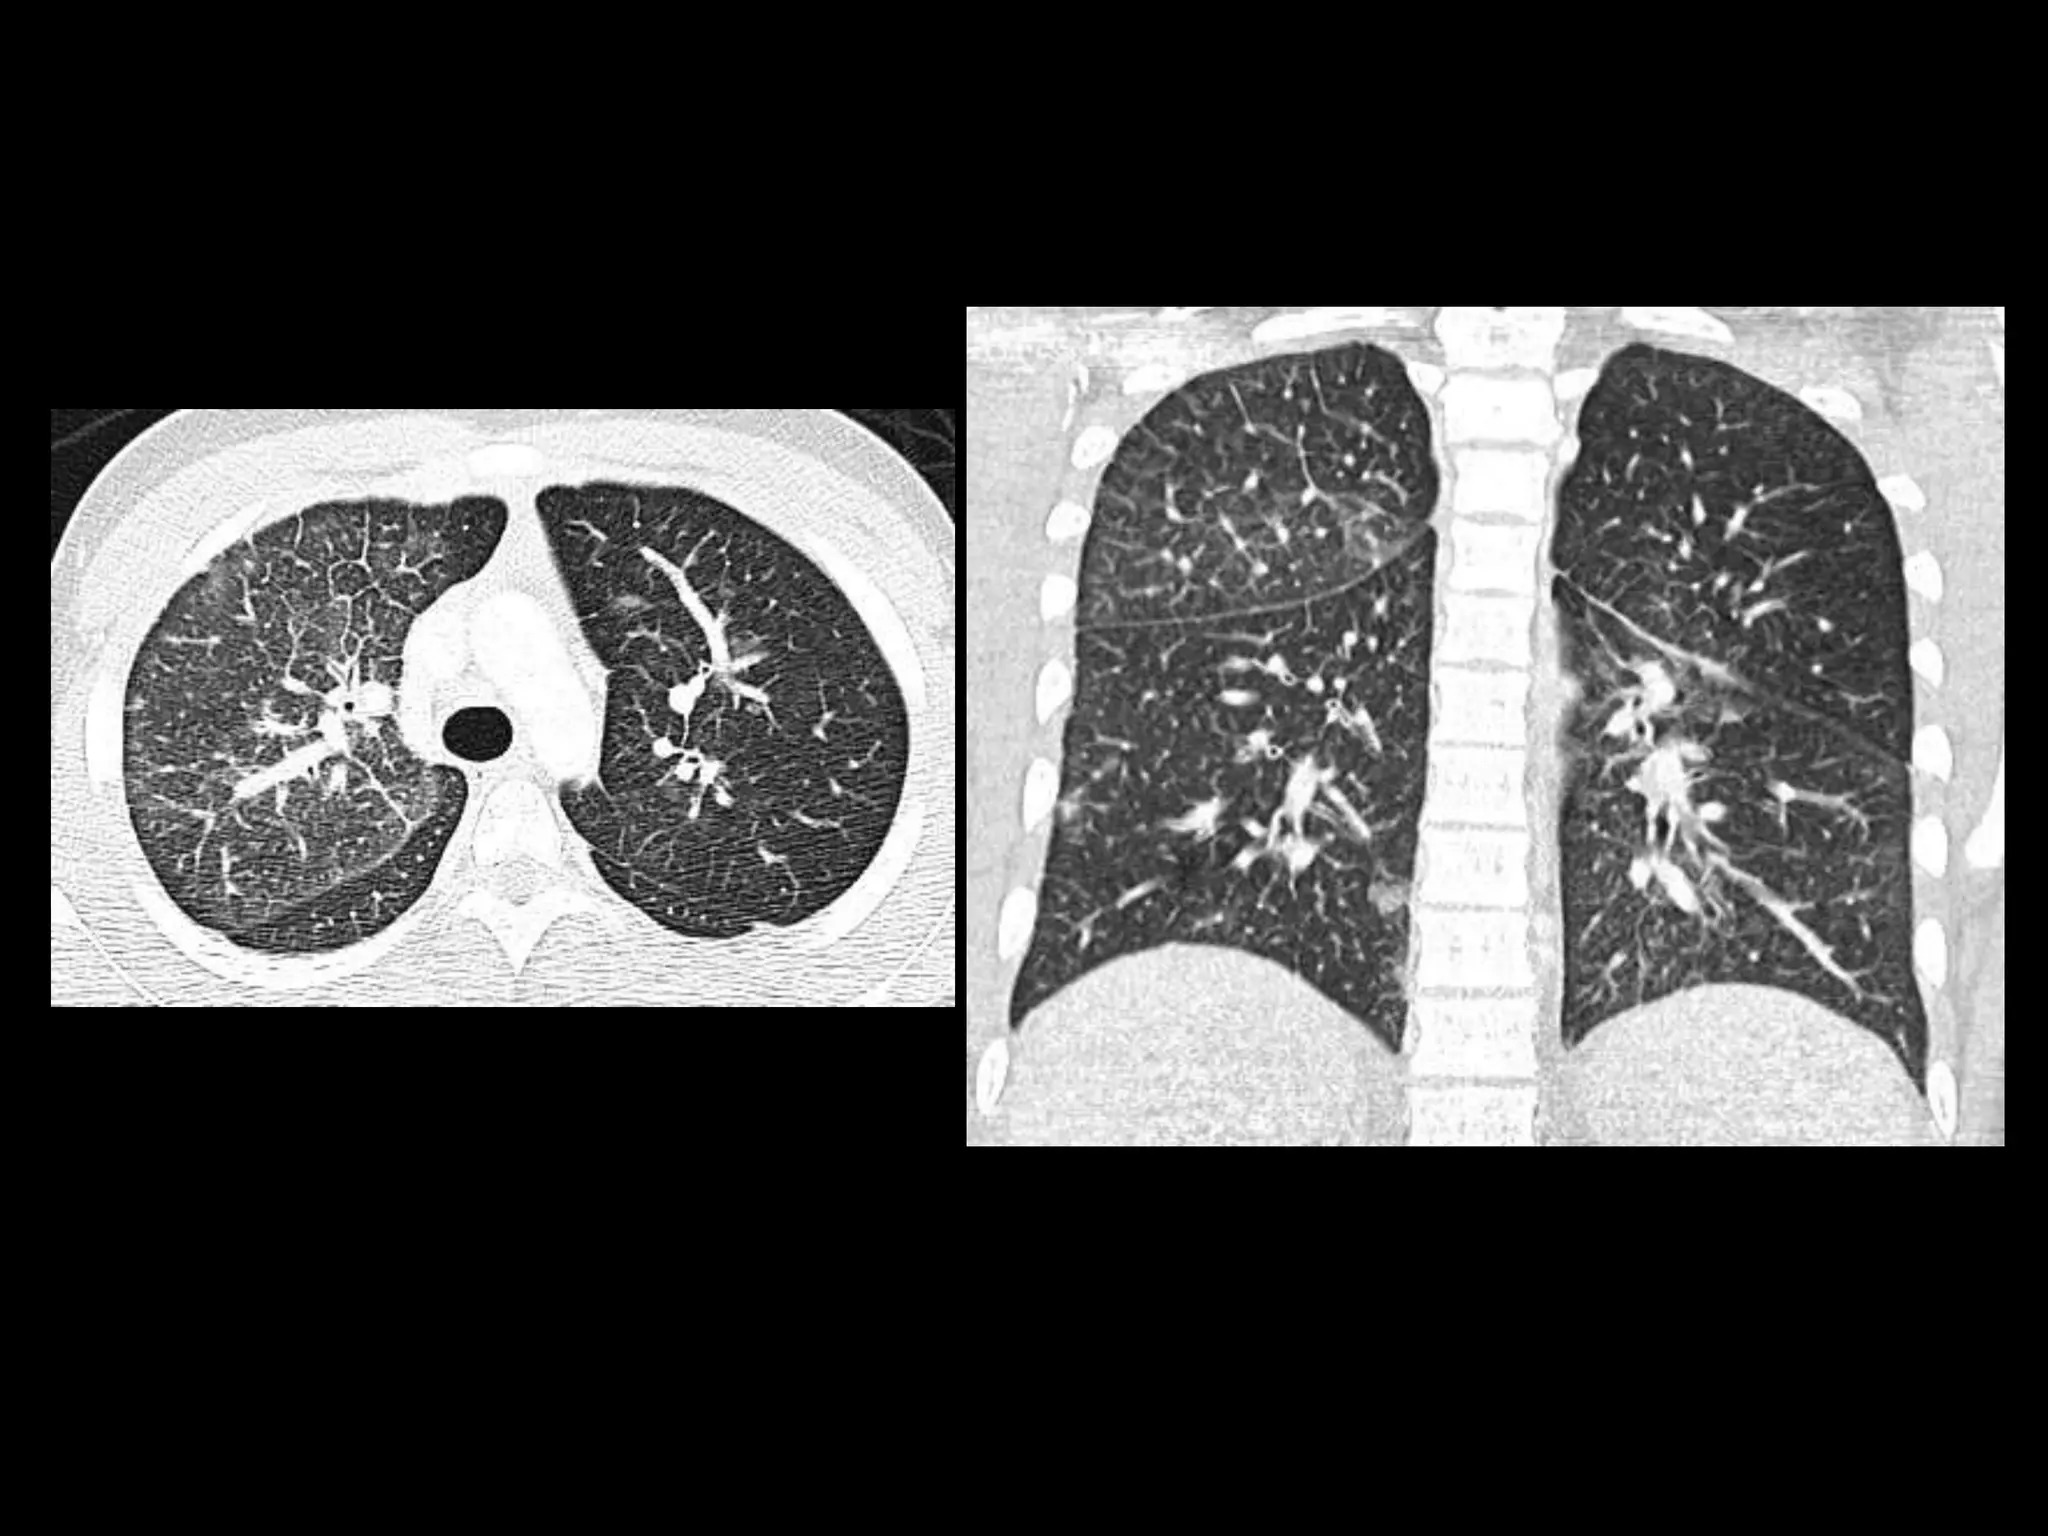

15 y.o. African American male with cough, shortness of breath, 10 # weight loss

Findings

• CXR – interstitial, septal

thickening

• Chest CT – septal

thickening, multiple small

nodules, ground glass opacities

• Abdominal CT –

infiltrative, indistinct left renal

mass

Pulmonary lymphangitic metastases

• Tumors: typically adenocarcinoma

– Breast, lung, colon, thyroid, pancreas

• CT Findings

– Interlobular septal thickening

– Nodules or reticulonodular changes

– Ground glass opacities

Metastatic renal medullary carcinoma

• Demographics:

– Seen almost exclusively in pts with sickle trait

– Age range = 11 – 39, Male: female=3:1

• Symptoms: pain, hematuria, wt loss

• Renal mass imaging features

– Infiltrative, associated necrosis, caliectasis

– More commonly right-sided

• Often widely metastatic at dx

– Pulm lymph spread is common